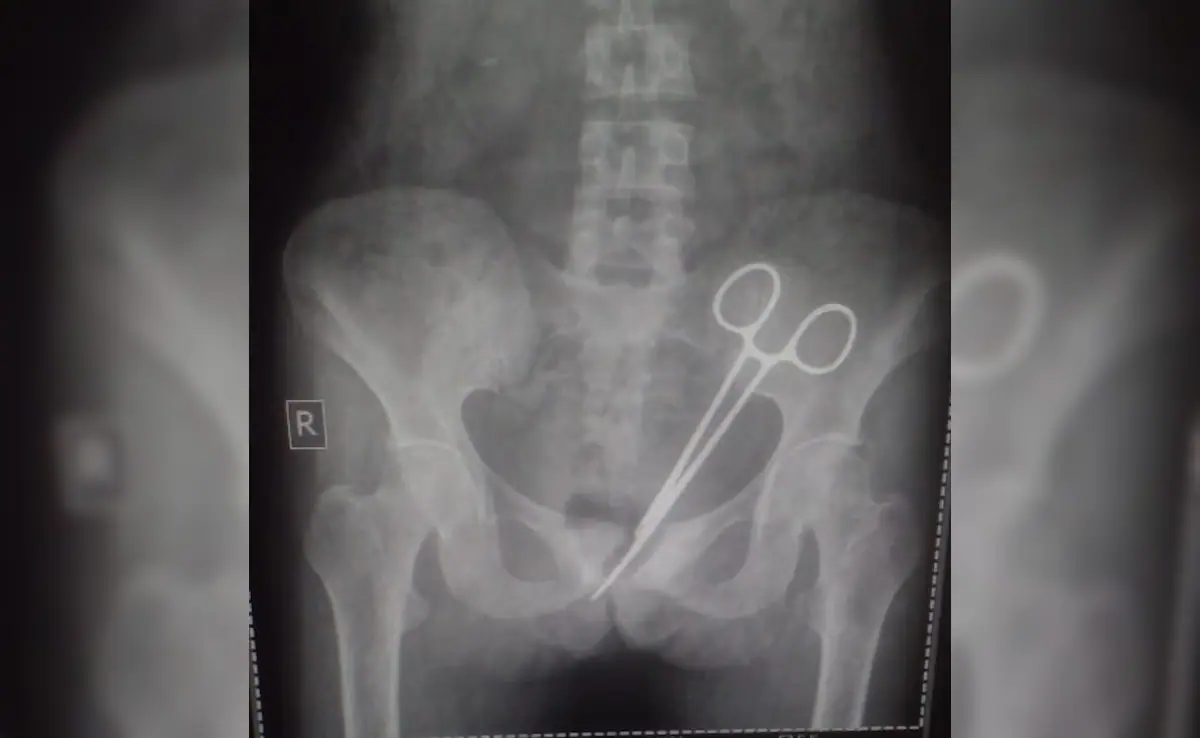

In an unbelievable case of medical negligence, a woman from Sikkim discovered that a pair of surgical scissors had been left in her abdomen for an astonishing 12 years. This horrifying revelation came to light only after she underwent a recent medical examination for persistent pain, which led to an X-ray that revealed the forgotten surgical tool lodged inside her body.

For over a decade, she suffered in silence, with doctors never suspecting the true cause of her pain. It was only during a recent health checkup, after the pain became unbearable, that an X-ray revealed the shocking presence of surgical scissors inside her abdomen. The news came as a devastating blow to Wangmo and her family, who are now demanding answers and accountability.